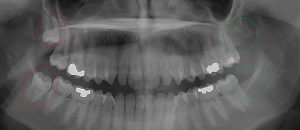

This 34 year old patient has all four third molars present (circled) and fully erupted into occlusion. They appear disease free…but are difficult to keep clean. 3rd molars are the most likely teeth to decay or have gum disease with a >98% probability that decay and gum disease will occur around all four teeth over this patient’s life time.